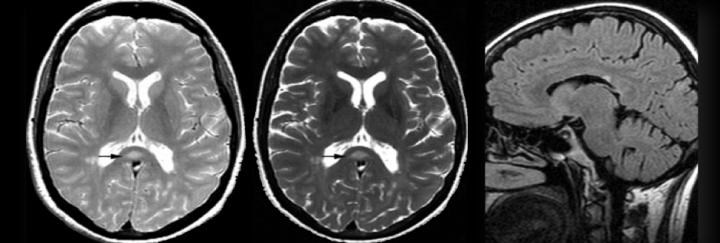

Konvansiyonel T2 lezyonları, aynı zamanda diffüz, büyük ve düzensiz hiperintens alanları da kapsar; bu görünüme “kirli ak madde” adı verilir. Bunlar sınırları belirsiz, özellikle oksipital horn çevresine yerleşen geniş lezyonlardır ve RRMS hastalarının yaklaşık %17’sinde tanımlanır.

- Beyin sapı / infratentoriyal lezyonlar

- Jukstakortikal lezyonlar

- Spinal kord lezyonları

Bu bölgelerdeki örnek lezyon alanları, MRG üzerinde İMG – MRG-1’den İMG – MRG-6’ya kadar olan görsellerde gösterilmiştir.

İMG – MRG-5: “Kirli ak madde” görünümü.

İMG – MRG-6: Jukstakortikal lezyonlar.